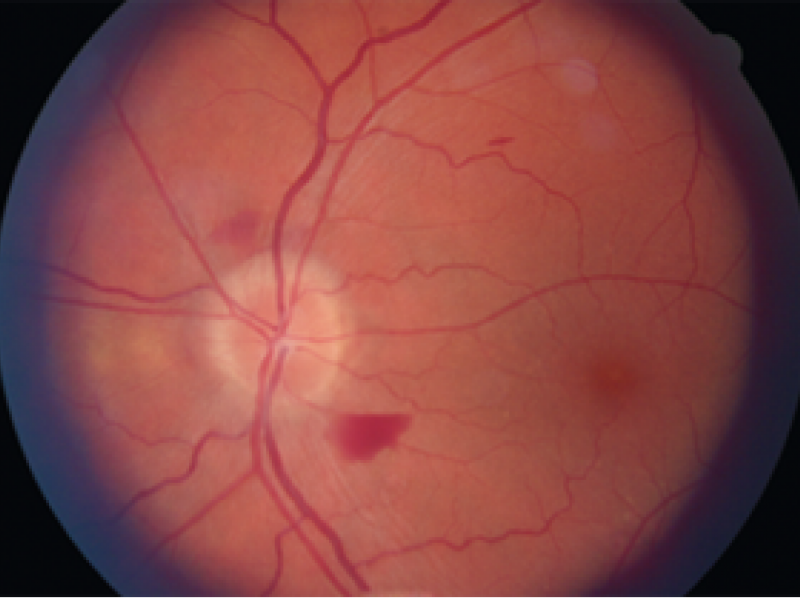

Fundoscopic Findings

EM Daily

September 06 2021

Findings in visual / eye emergencies on fundoscopic exam By